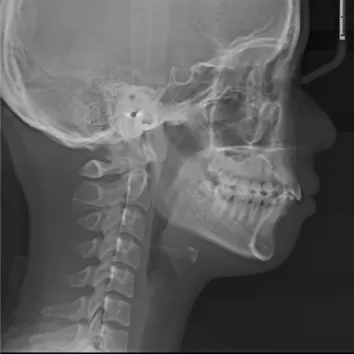

Female, 25 years old. Chief complaint: protruding and misaligned teeth, requiring orthodontic treatment.

X-rays before treatment

[Panoramic Radiography/Lateral Cephalogram]